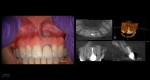

This was interesting because a root frac ture was seen where the prior apico was done. The MTAS was removed and Brassler putty used in this case. Will take a 1 yr CBCT and we will know more. Don’t usually get so much scar formation–so this was surprising…..